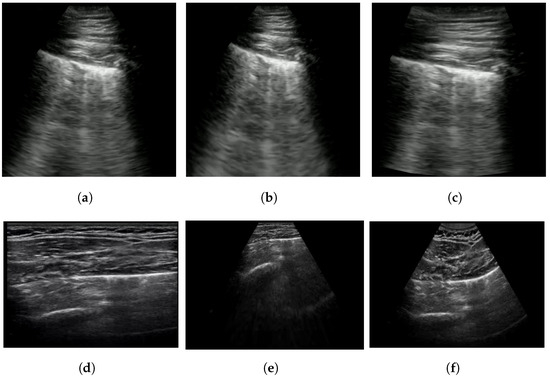

Extended linear–convex ultrasound augmentation learning aims to utilize the maximum amount of POCUS data while accounting for the visual appearance differences caused by employing different probes for capturing POCUS images. For instance, convex probe images have a larger field of view, with a cone-shaped viewing window that varies in angle and form across devices (Figure 1). Linear probe images, on the other hand, have a more restricted field of view and a linear viewing window [35], leading to distorted visual content compared to convex probe images.

Figure 1. An example of ultrasound images with different viewing windows. The bounds of the viewing windows are marked in red.